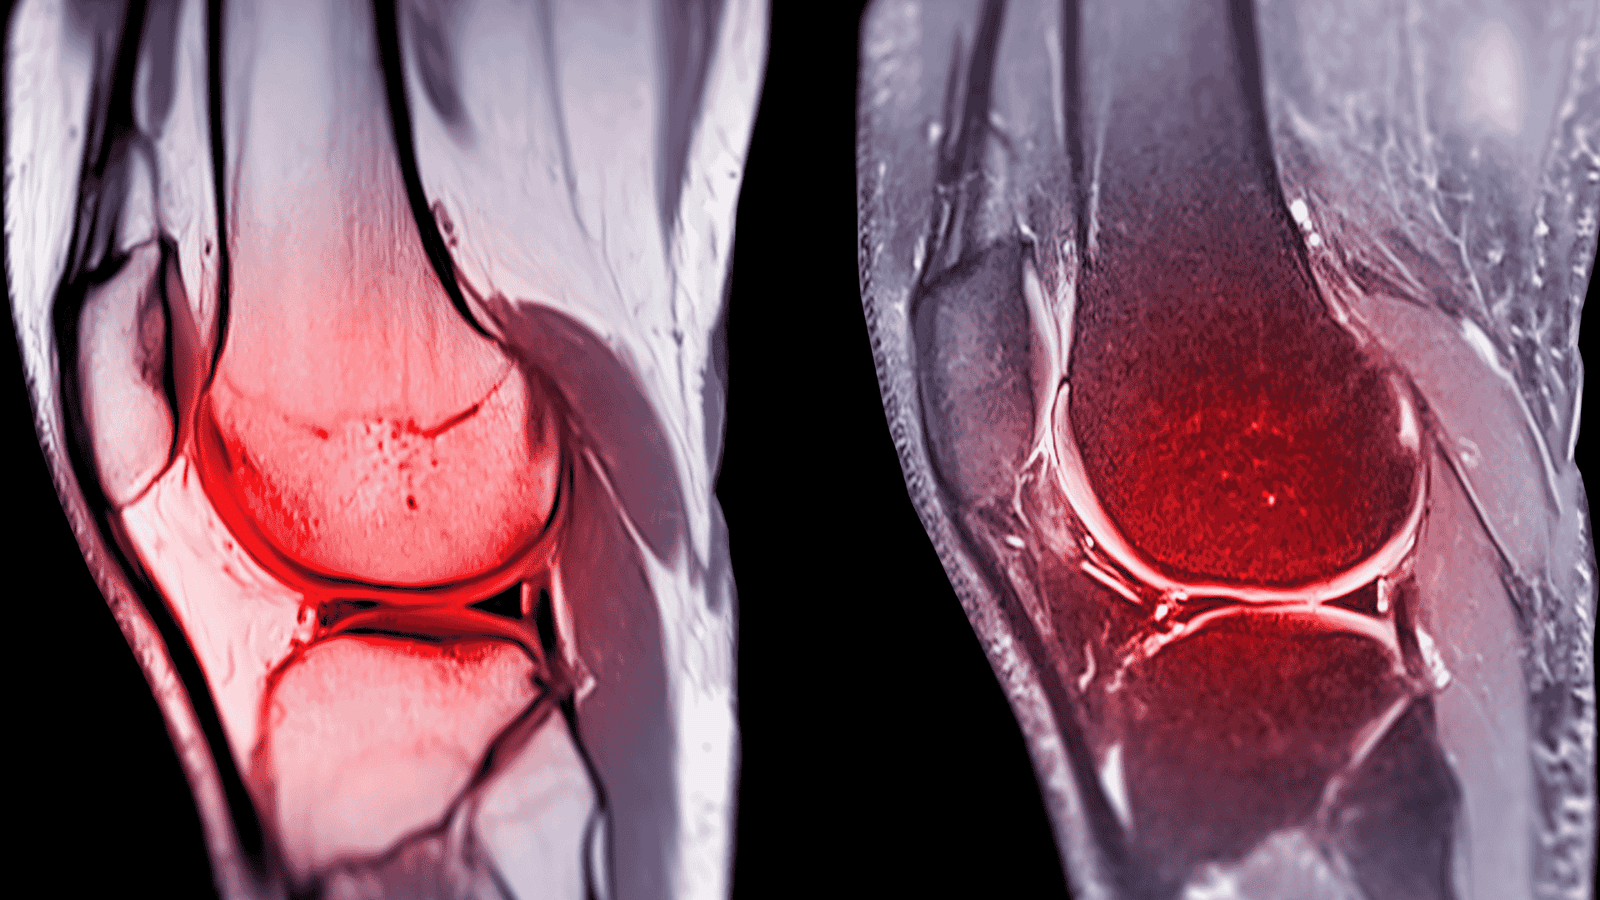

- Ressonância magnética: exame de escolha para visualizar a ruptura e avaliar estruturas associadas, como meniscos;